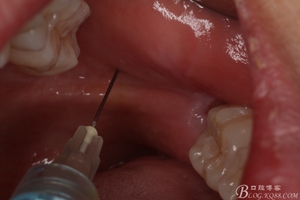

圖5.術(shù)前做好全面的檢查和風險評估,開始局部無痛麻醉。